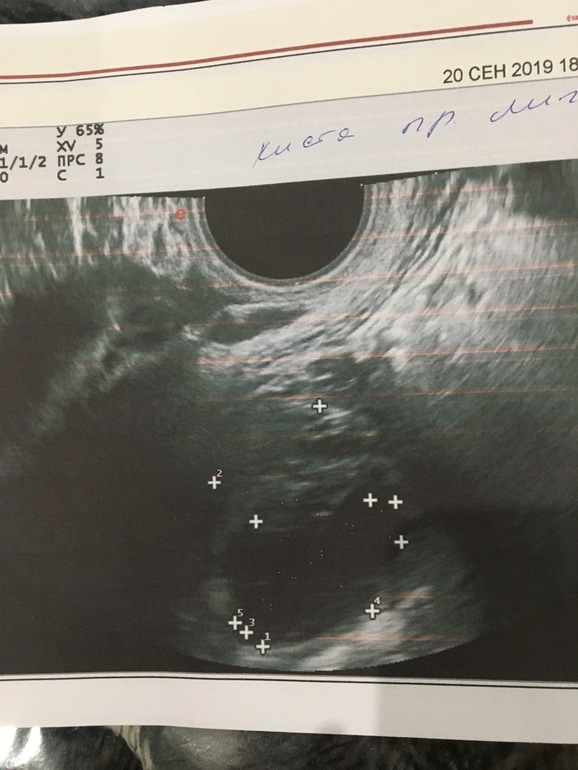

По фото УЗИ у вас видно совулировавший фоллик

А она говорит, что это киста...я уже тоже думала, что возможно она просто перепутала🙄😬

Жидкость в позадиматочном пространстве говорит о свежей О, возможно она случилась вот вот, буквально. Жт еще не сформировано, ему нужно время. В пя большое образование похоже на ДФ. Либо их было 2, либо с него и надуло жидкости. Но узи и правдо странное. Переделайте через пару дней, если О все таки была будет ЖТ.

А вот и фото ПЯ, левого она не сделала🤬